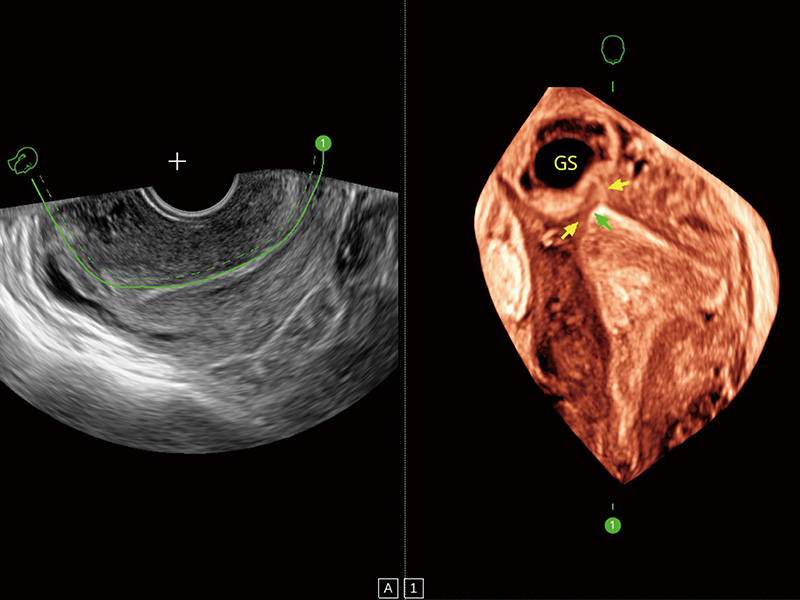

腔内容积探头

腔内三维成像技术获得显著提升,超大扇角在满足日常基础扫查的同时,支持卵泡自动测量及多种三维渲染模式,为您提供更多的诊断信息,尤其是在子宫畸形的诊断,内膜及肿瘤占位观测中起到了重要的作用。

输卵管间质部妊娠